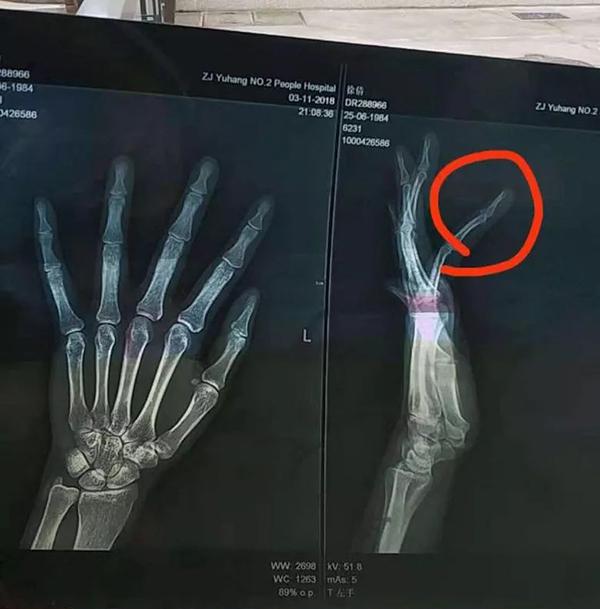

当地医院x线片考虑右手无名指中节骨折,医院建议手术治疗

林先生左手无名指骨折,已接受手术